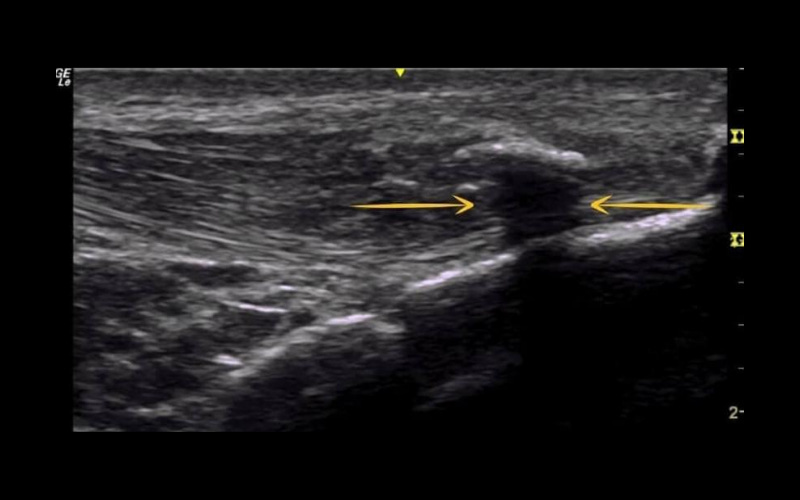

Sombra acústica posterior

"Ocurre cuando el haz del ultrasonido entra en contacto con densidad mineral ósea, generando profundo a él una sombra."

En este caso nos encontramos en un tendón rotuliano. Se observa una calcificación y cómo se genera una sombra (señalado con flechas amarillas) que corresponde a un artefacto. ¿Podríamos saber con ecografía si una calcificación es de densidad dura o blanda?

¡Por supuesto!